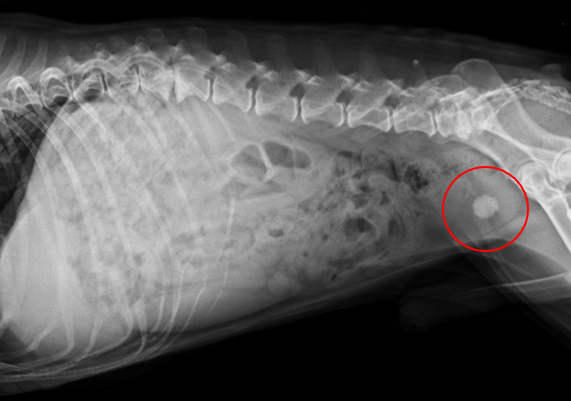

犬の膀胱結石とは、尿をためる袋とも言うべき膀胱に結石を生じた状態を言います。 膀胱 (ぼうこう)とは腎臓から送られてくる尿を一時的に溜める袋状の器官であり、左右の腎臓から尿管を通して尿を受け取り、尿道を通して体外に排出します。 膀胱結石は尿路結石の中で最も発症頻度が高く、多くは 膀胱炎 に引き続いて起こります。 尿道が短くて細菌の進入. うえの犬猫病院は犬 リンク 採用情報 お問合せ 症例紹介 膀胱結石 膀胱結石とは 膀胱結石は膀胱炎や細菌感染、尿路閉塞の原因になります。特に尿路閉塞が危険で、結石が排尿路に詰まると急性腎不. Case42 膀胱結石の犬の1例 血尿と頻尿を主訴に来院した8歳の雄のワンちゃんです。 4ヶ月前にも同様の症状がありましたが抗生剤の投与で改善しました。 今回も同様の治療を試みましたが間欠的に血尿が続き、再発ということもありレントゲンと超音波検査を実施しました。 レントゲン検査では膀胱領域に数ミリの結石を認め、超音波検査でも複数の結石が確認され.

犬 膀胱結石・尿道結石 チワワ 10歳11ヶ月齢 去勢オス 71kg 頻尿と血尿、排尿障害を主訴に来院 腹部と陰茎の触診検査にて結石症が疑われたため、 レントゲン検査を行い、膀胱結石および尿道結石、腎臓結石と診断した 尿道内にぎっしりとつまった結石は、カテーテルにて膀胱内に押し戻し、膀胱切開にて膀胱結石を摘出した 腎臓結石はに対する外科処置は、腎臓. 犬の膀胱結石 更新日時: ミニチュアダックスフンド、オス (去勢)、11歳 《主訴》血尿、排尿しづらい (少量ずつしか出ない) 《検査》①腹部レントゲン検査 膀胱に結石と思われる不透過性陰影を多数確認 ②腹部超音波検査 膀胱内に結石と思われるシャドーを引く高エコー物を多数確認 ③尿.